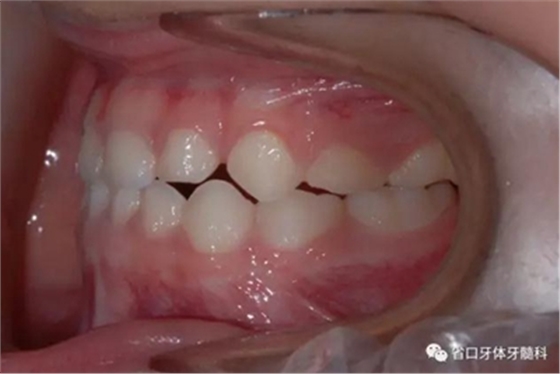

圖4 正面牙相(2015年1月)

圖11 局部牙性前牙反合可使用頜墊舌簧糾正